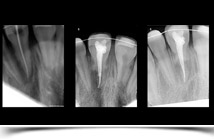

Mediante radiografías digitales intrabucales, podemos explorar con mayor exactitud la patología dental y periodontal.